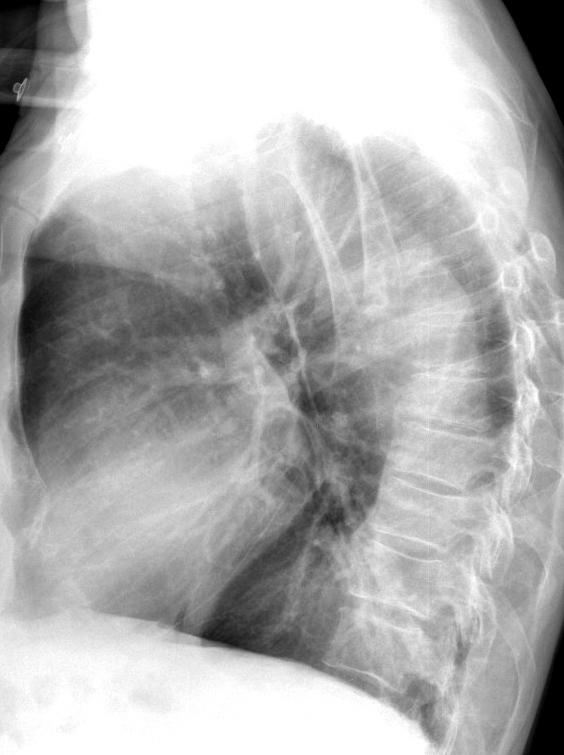

Bóc tách ĐM chủ ngực

» Thông tin: Nam giới – 72 tuổi.

» Lâm sàng: Đau ngực.